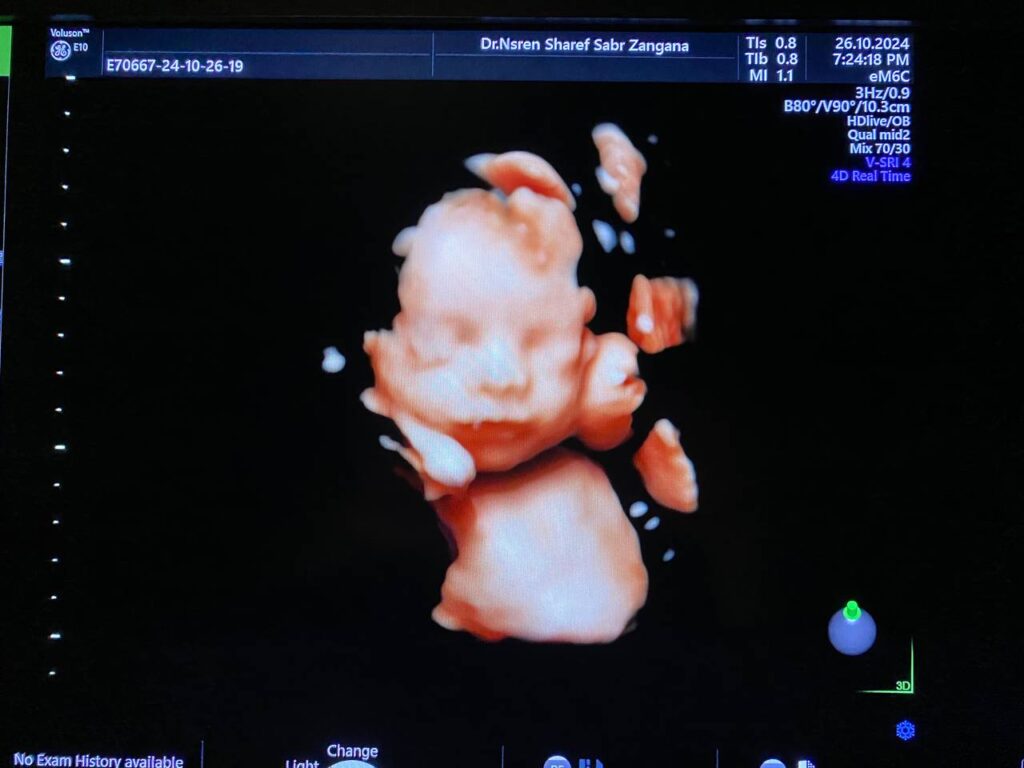

Brain: mild to moderate dilated lateral ventricles 16mm, with remaining cerebral mental about 13mm, dilated third ventricle, normal fourth ventricle, Picture mostly of Hydrocephaly due to aqueduct of Sylvius stenosis